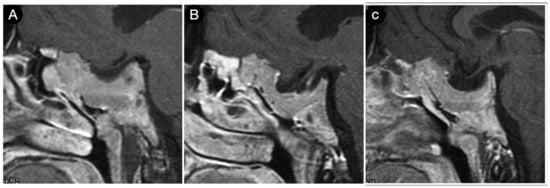

3.10. Postoperative Pituitary Apoplexy after Trans-Sphenoidal Surgery